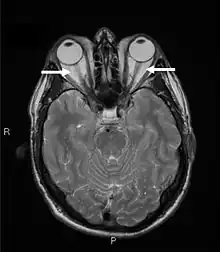

Magnetic resonance imaging of the orbits, showing congestion of the retro-orbital space and enlargement of the extraocular muscles (arrows), consistent with the diagnosis of Graves' ophthalmopathy.

Orbital imaging is an interesting tool for the diagnosis of Graves' ophthalmopathy and is useful in monitoring patients for progression of the disease. It is, however, not warranted when the diagnosis can be established clinically. Ultrasonography may detect early Graves' orbitopathy in patients without clinical orbital findings. It is less reliable than the CT scan and magnetic resonance imaging (MRI), however, to assess the extraocular muscle involvement at the orbital apex, which may lead to blindness. Thus, CT scan or MRI is necessary when optic nerve involvement is suspected. On neuroimaging, the most characteristic findings are thick extraocular muscles with tendon sparing, usually bilateral, and proptosis.